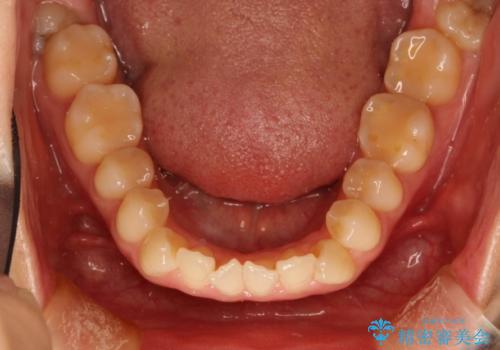

前歯のガタガタをインビザラインで目立たず矯正

- 目立たずに前歯を矯正したいとのことで来院されました。

歯と歯の間にわずかに隙間を作りスペースを確保し、インビザラインにて矯正を行うこととなりました。

前歯の微調整に少し時間がかかりましたが、整った歯並びにすることができました。